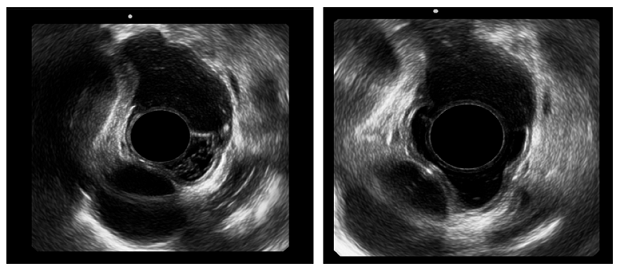

Ante el hallazgo, se decidió realizar la EUS radial esofágica en la que se encontró una lesión dependiente de la tercera capa esofágica, pero de características hipoecoicas más que anecoicas, por lo que se realizó una EUS-FNA con estudio citológico rápido. Se encontró abundante material mucoso que evidenció la presencia de células epiteliales y contenido de mucina, sin evidencia de cambios citopatológicos malignos (Figura 2).

Ante los hallazgos que apoyaron el diagnóstico de quiste de duplicación sin malignización, se procedió a realizar una marsupialización del quiste bajo anestesia general en una sección de la pared luminal del mismo con electrobisturí de punta endoscópico. Se realizó un corte de 20 mm sobre el cénit de la lesión luminal con disección por pasos hasta la submucosa; se logró el completo drenaje de la lesión y su inspección endoscópica completa, y se encontró una cavidad ciega, recubierta por un epitelio pálido, sin características de malignidad (Figura 3).